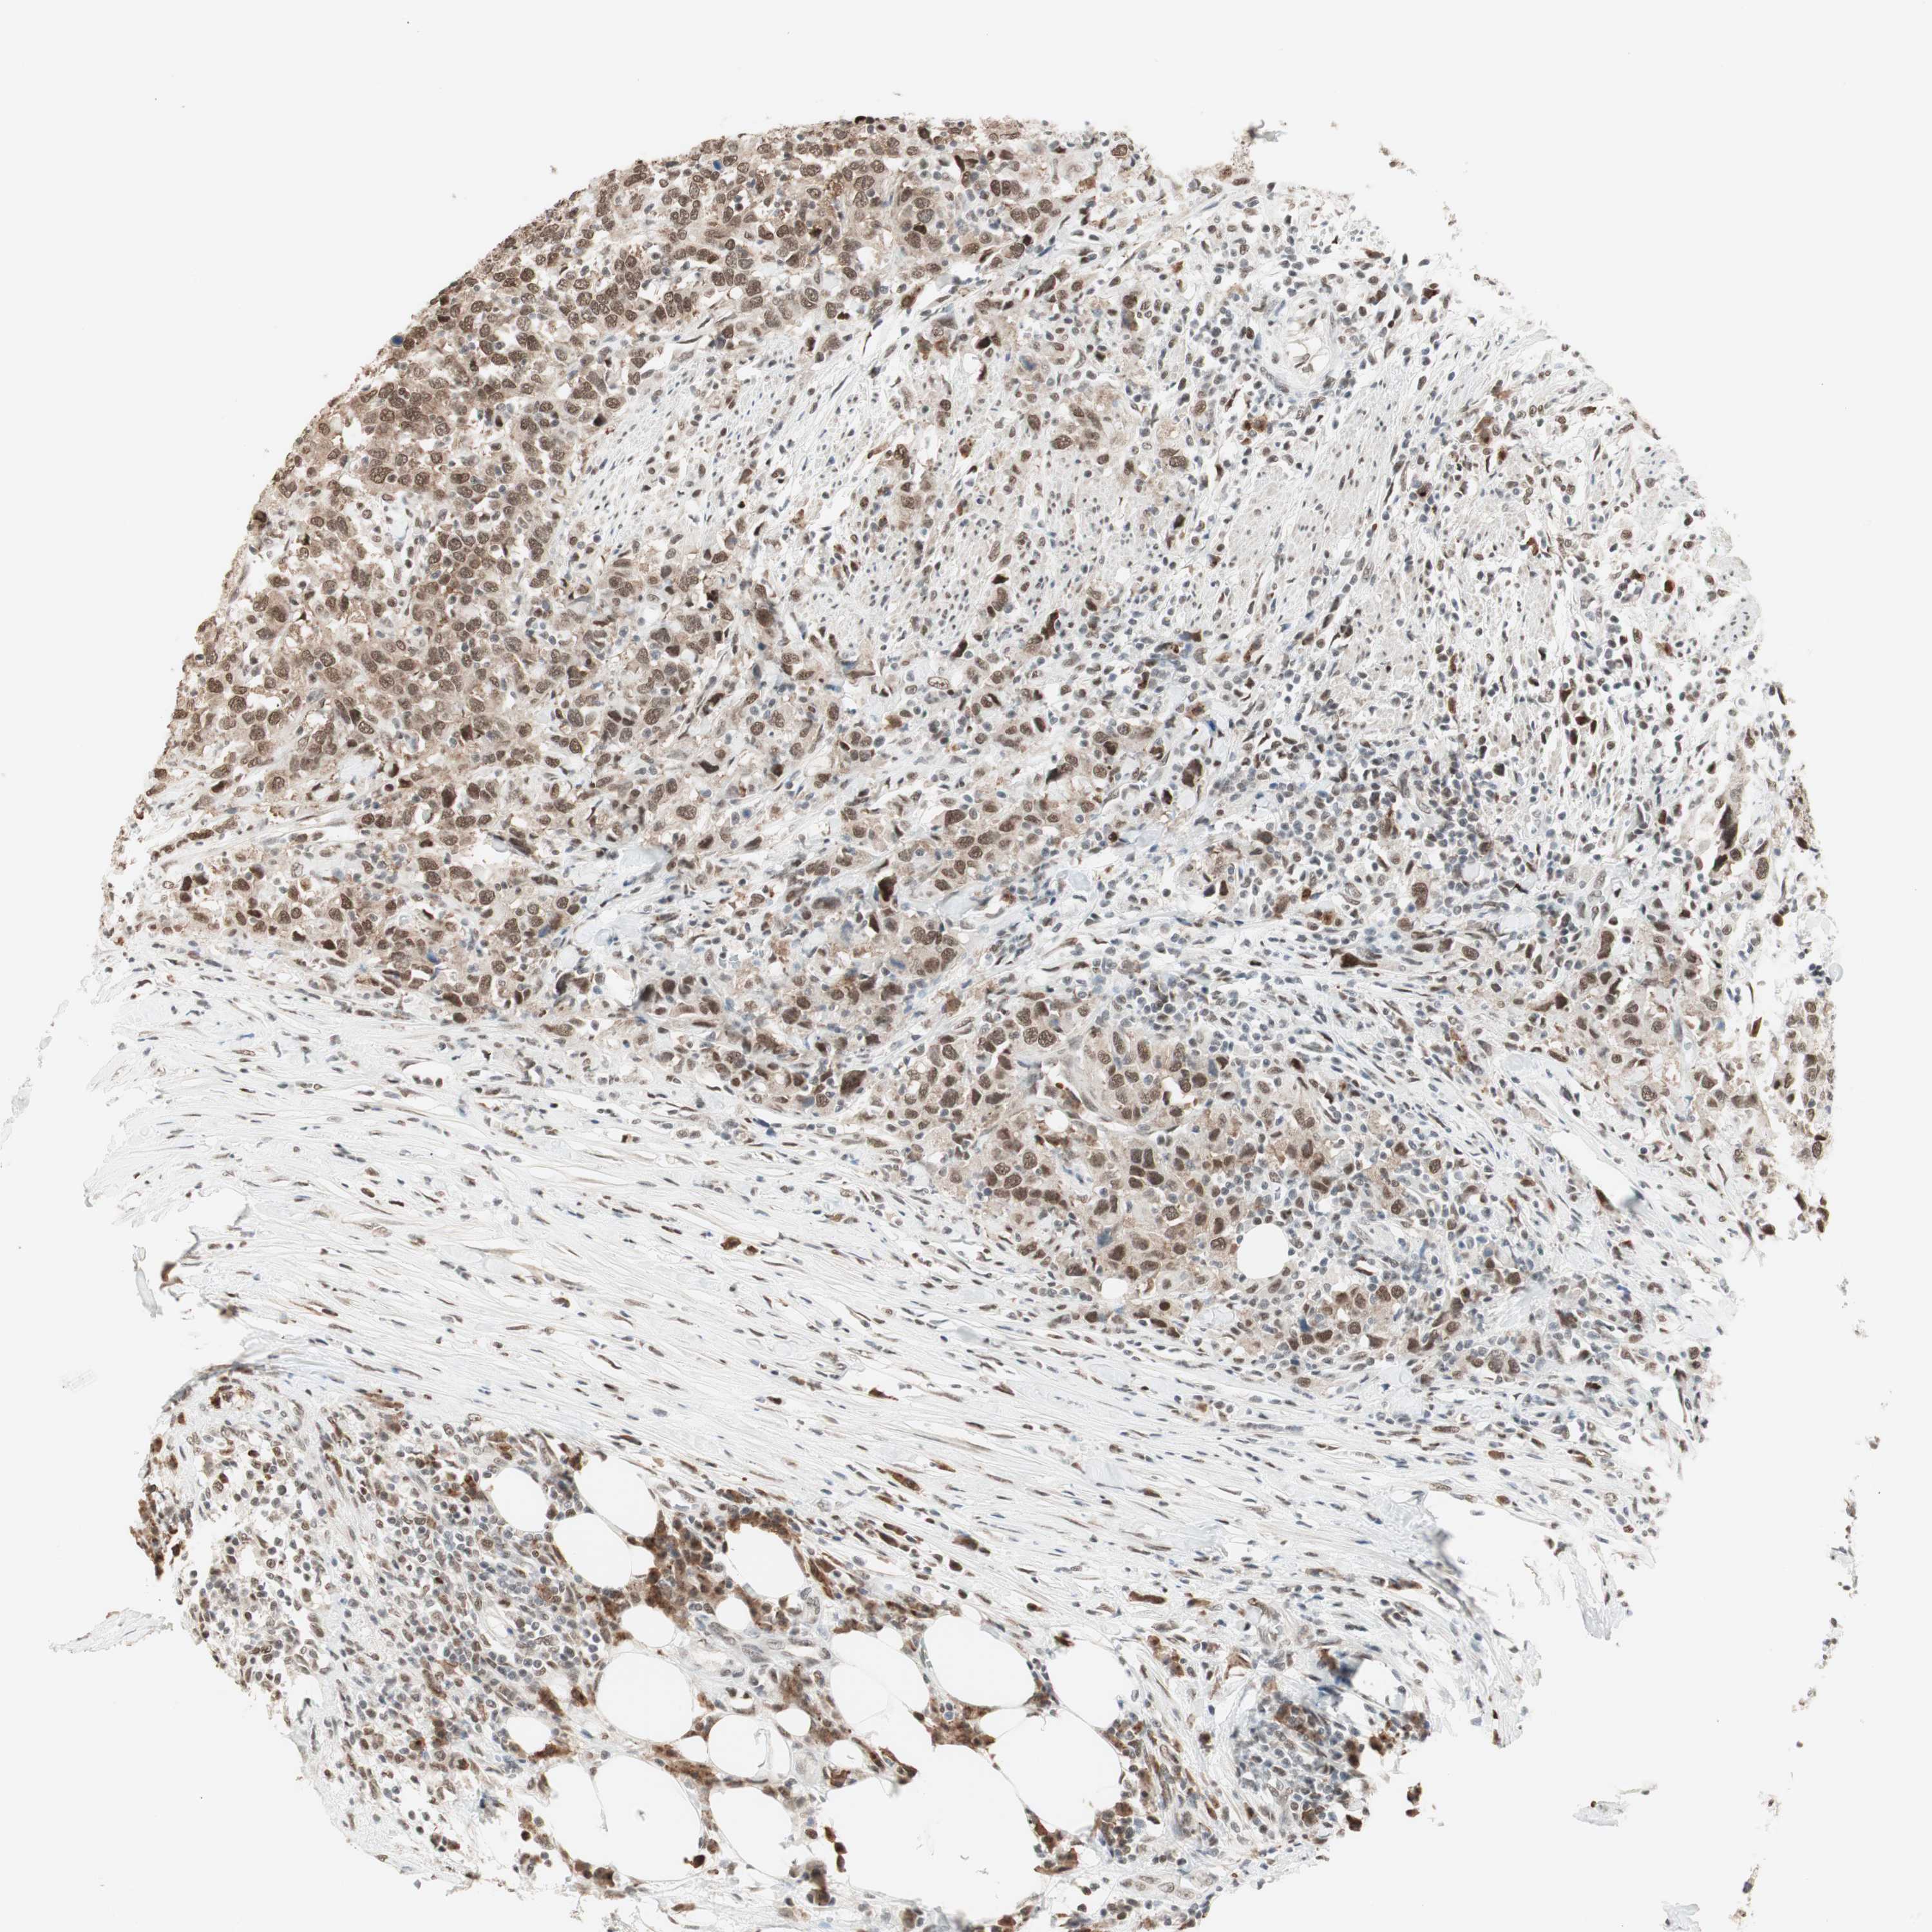

UROTHELIAL CANCER - Protein expressioni

A mouse-over function shows sample information and annotation data. Click on an image to view it in a full screen mode. Samples can be filtered based on level of antibody staining by selecting one or several of the following categories: high, medium, low and not detected. The assay and annotation is described here.

Antibody stainingi

Antibody staining in the annotated cell types in the current human tissue is reported as not detected, low, medium, or high, based on conventional immunohistochemistry profiling in selected tissues. This score is based on the combination of the staining intensity and fraction of stained cells.

Each image is clickable and will lead to virtual microscopy that enables deeper exploration of all samples and also displays staining intensity scores, fraction scores and subcellular localization as well as patient and tissue information for each sample.

Antibody HPA003916

Antibody CAB037318

Staining

High

Medium

Low

Not detected

Intensity

Strong

Moderate

Weak

Negative

Quantity

>75%

75%-25%

<25%

None

Location

Nuclear

Cytoplasmic/membranous

Cytoplasmic/membranous,nuclear

Urothelial carcinoma, Low grade

Urothelial carcinoma, High grade

Urothelial carcinoma, NOS